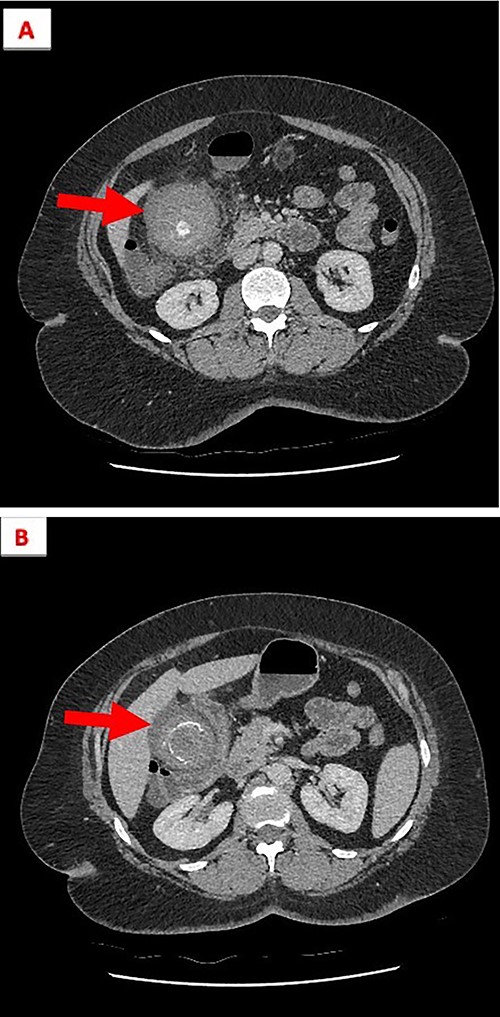

Coronal view of gall bladder with high-density fluid and calculi.